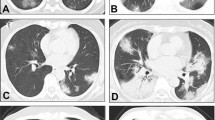

We investigated the influence of age and CT values on recovery outcomes, as illustrated in Fig. 3, which presents recovery times for patients treated with Paxlovid (Fig. 3-a), Azvudine (Fig. 3-b), and those without antiviral therapy (Fig. 3-c). Our results indicate that Azvudine provided considerable clinical benefits for patients aged 50–80, although findings for patients aged 35–50 and those over 80 years should be interpreted with caution due to limited sample sizes.

Additionally, our analysis revealed differential effects of the antiviral drugs on improving lung CT values and symptom relief. Paxlovid exhibited notable efficacy, particularly in patients with moderate disease severity. Patients classified as moderate showed substantial benefits from both Azvudine and Paxlovid, whereas the impact was markedly diminished in those with severe disease. These findings underscore the pivotal role of antiviral agents in mitigating disease severity and enhancing lung function, particularly in targeted patient subgroups.

Analysis of the impact of CT values and classifications at different ages and periods on the effectiveness of taking different drugs. (a), (b), and (c) Shows how different age groups influence recovery times when using different drugs. This helps us understand age-related recovery variations with various medications. (d) Illustrates how different drugs affect CT values, a critical diagnostic measure in COVID-19. This reveals the impact of drug choices on diagnostic indicators. (e) Examines how different drugs impact recovery times among different symptom classifications. It highlights variations in drug efficacy for distinct groups of COVID-19 patients.